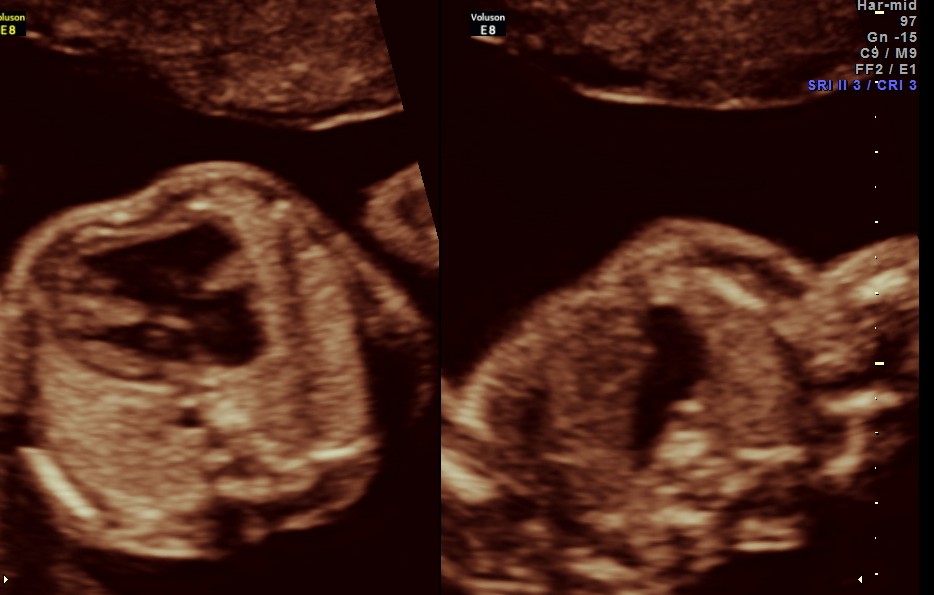

The cardiac axis appeared to be abnormal .

4 chamber view is given below .

another view of the above two